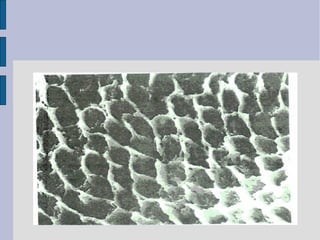

Acid Etching

A physical process that creates a

microscopically rough enamel

surface (enamel tags)

 first successful technique developed

to bond dental materials to tooth

structure

 acid used id 37% ortho-phosphoric

acid

Enamel Etching

 37% ortho-phosphoric acid

 dissolves the periphery of enamel

rod, or the core of the rods or both

 over-etching results to formation of

crystals (precipitates) that inhibits

bonding

 built-in quality control check – if

properly etched it appears frosty or

chalky white.